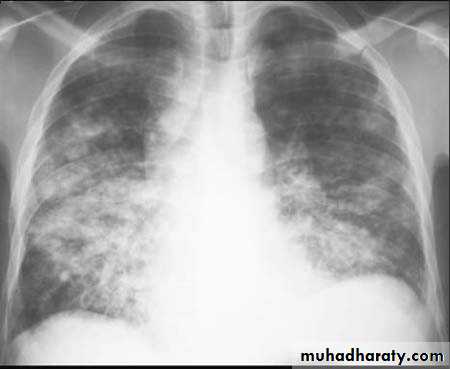

Lobular consolidation ( broncho or lobular pneumoniaCXR of adult ,PA and lateral views show:Patchy consolidation in both lung fields (diffuse) mainly in the lower zonesNormal heart size

Very important to consider that pulmonary edema in normal sized heart have close similar appearance to broncho pneumonia

The important Golden Key differentiation is the cardiac size being enlarged in pulmonary edema .